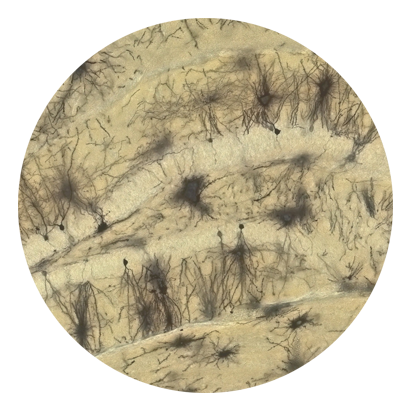

高尔基染色